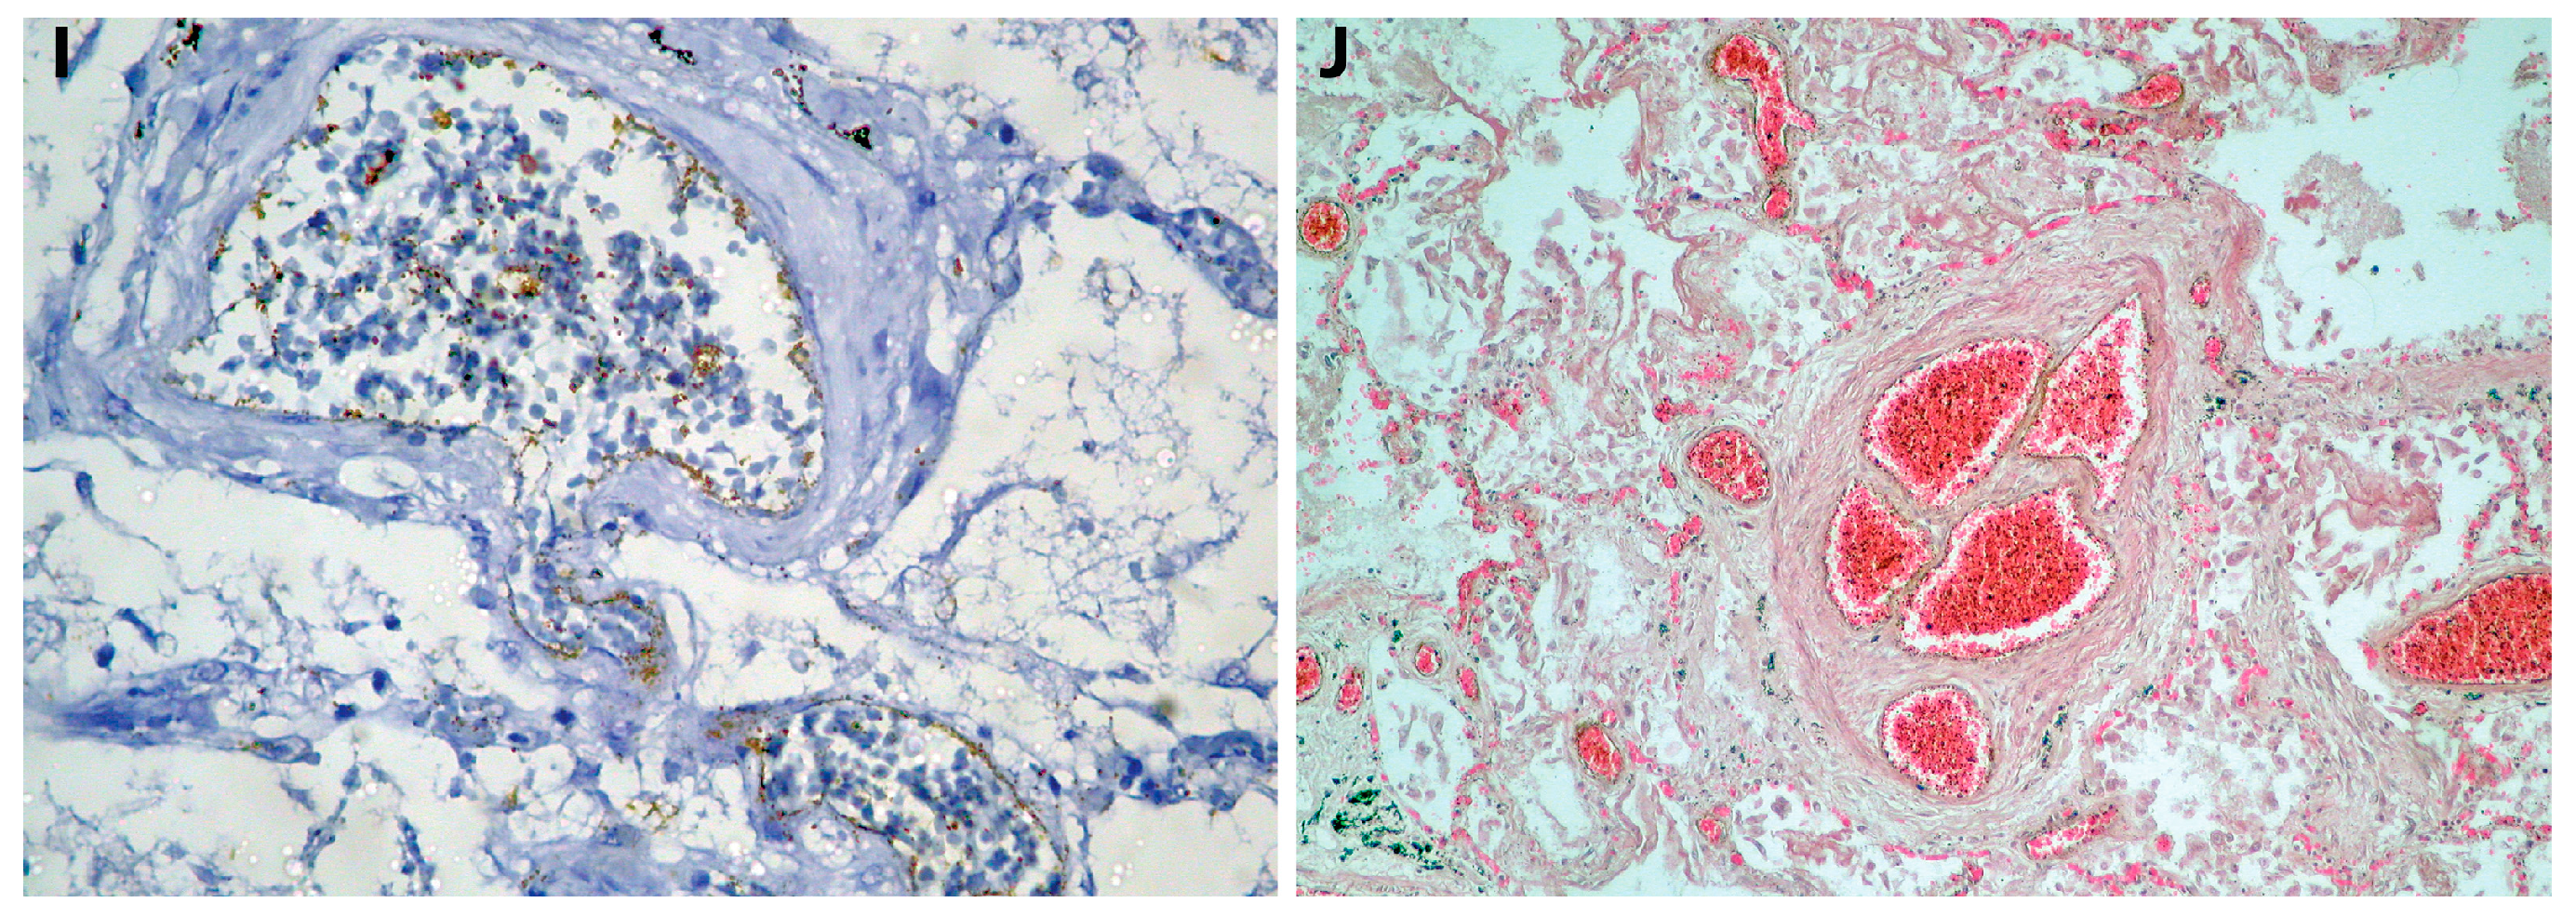

| 4, F, 69 | Department of Pathology, County Emergency Hospital Deva | Autopsy (Figure 1D–E) | B.1.617.2/ Positive for screening (L452R) | Acute pulmonary edema, DAD 1, focal DAD 2 (Figure 2C–D), multifocal organizing pneumonia, pulmonary microthrombosis, plexogenic lesion (Figure 2J) | Positive proteins of SARS-CoV-2 in endothelial cells (endothelithis COVID-19) (Figure 2I) |